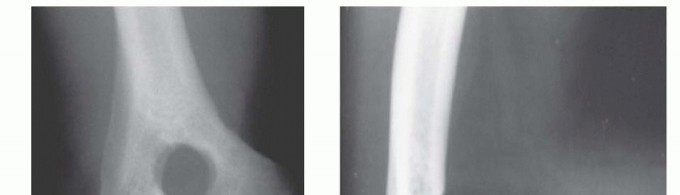

FIG 1 • A. Lateral radiograph of a 50-year-old heavy laborer's elbow. The patient had severe pain at the extremes of motion. The radiograph reveals characteristic osteophytes of the olecranon and of the coronoid process. B. AP radiograph of the elbow (same patient). This view shows ossification and osteophytes of the olecranon and coronoid fossa. C. Lateral oblique radiograph. This view provides better visualization of the radiocapitellar and radioulnar joint. There is an osteophyte at the tip of the olecranon, which causes pain during full extension. Ulnar nerve symptoms may also be present, owing to excessive osteophyte formation. They should actively be sought out because they may influence treatment decisions and even direct the surgical approach.Physical examination may reveal a positive Tinel sign and a positive elbow flexion test, with decreased sensation and weakness in the ulnar nerve distribution. Cubital tunnel syndrome may be present in up to 20% of patients.

Anteroposterior (AP), lateral, and oblique radiographs (FIG 1) are diagnostic and illustrate characteristic features of the condition.The AP view should be taken with the beam perpendicular to the distal humerus for distal humerus pathology and perpendicular to the radial head for proximal forearm pathology. These views will show ossification and osteophyte formation of the olecranon and coronoid fossae.The lateral view should be taken in 90 degrees of flexion with the forearm in neutral rotation. This view will show an anterior osteophyte on the coronoid fossa and process and a posterior osteophyte on the olecranon fossa and process.The lateral oblique view provides better visualization of the radiocapitellar joint, medial epicondyle, and radioulnar joint.The medial oblique view provides better visualization of the trochlea, olecranon fossa, and coronoid tip. A cubital tunnel view may be useful if there is ulnar nerve symptomatology.Computed tomography or a lateral tomogram are helpful for preoperative planning to assess the presence and location of loose bodies and subtle osteophyte formation (especially in earlier stages).